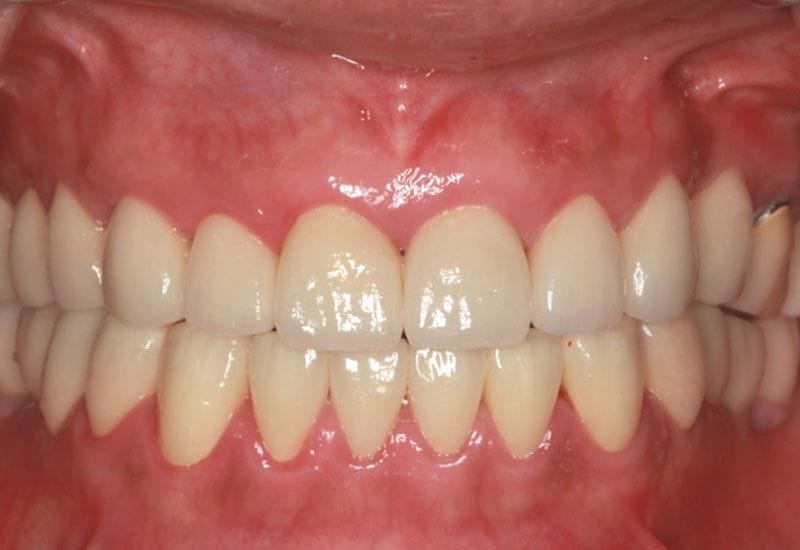

假牙完成後 病患恢復咬合功能,微笑曲線的建立與全瓷假牙的治療,讓病患有自信的笑容,牙齒也因為有了保護而減低敏感度,此後建議病患定期回診 並已製作咬合板 請病患於睡覺時配戴 防止夜間磨牙的高咬合力量造成假牙或牙齒的損害

如圖13.14

圖13

圖14